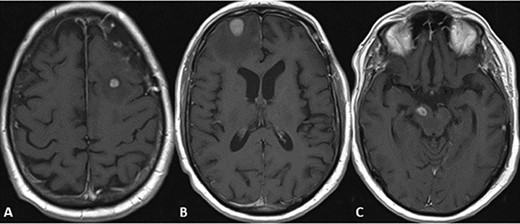

CASE

CT and MRI scans of the head indicating a large hemorrhagic enhancing lesion in the left frontal lobe with surrounding edema causing a rightward midline shift.